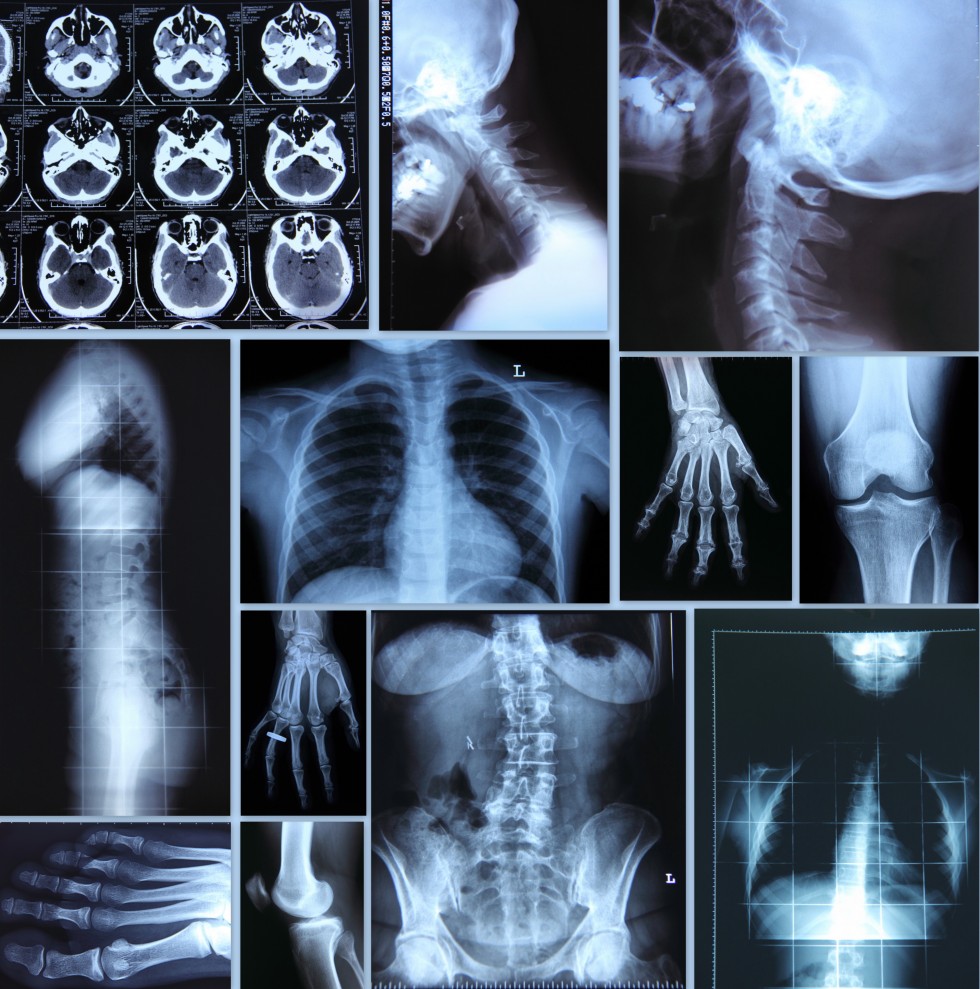

The physicians of Professional Radiology, in conjunction with our partner hospitals, provide a full range of diagnostic radiology services. We continuously investigate new procedures and techniques to better serve our patients. We offer the latest technology and service in a variety of diagnostic areas including:

- X-ray/fluoroscopy

- Magnetic Resonance Imaging

- Computed Tomography

- Ultrasound

- Mammography

- Positron Emission Tomography

- Nuclear Medicine